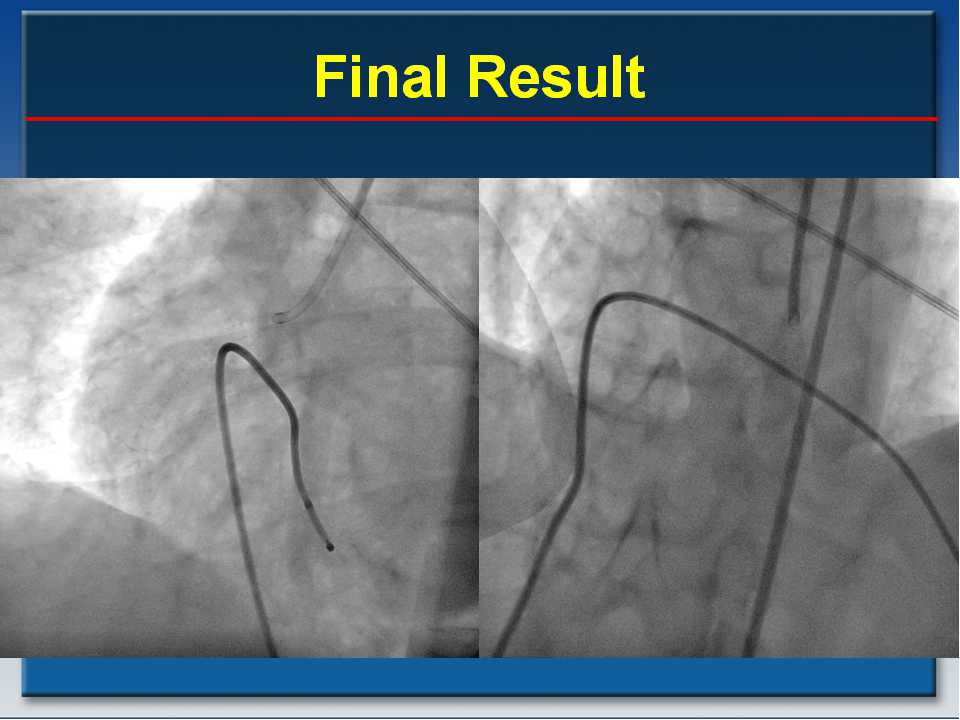

Prevention of Distal Embolization An unmet need in primary PCI